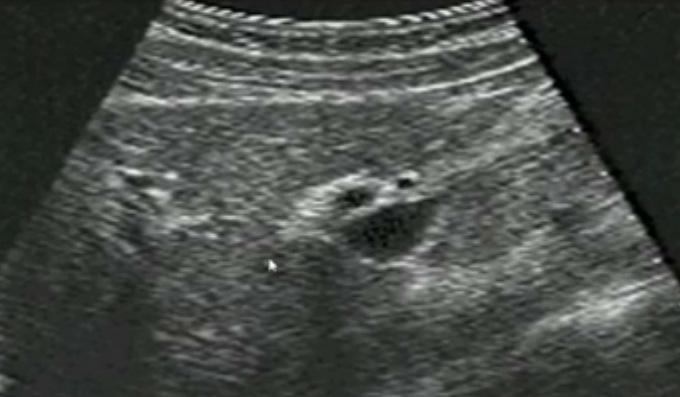

一、正常胆囊超声图像有的时候经常发现检查不到胆囊,其实有几种可能性,检查人员的技术不过关没发现胆囊,就要找上级医生会诊,如果还是没找到的话就不是技术问题。结石或肿瘤充满胆囊,使其液腔消失,慢性胆囊炎使得胆囊萎缩或胆囊壁肥厚而囊腔消失患者已进食,胆囊处于胆汁排空的状态,胆囊先天性过小或缺失;胆囊位置极端异常(可能很低或位于左侧)胆囊切除术后(注意询问病史)。